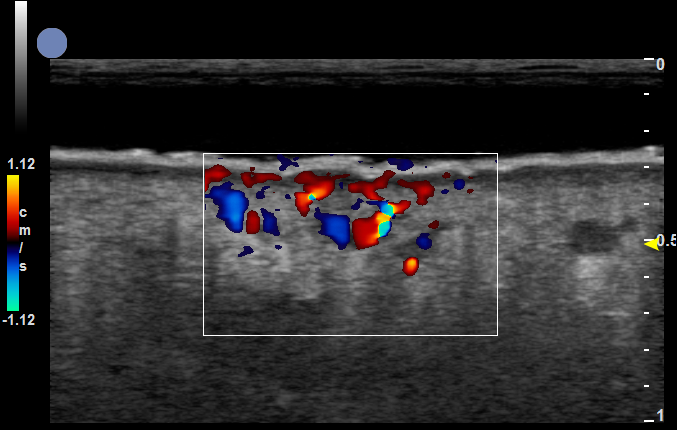

增殖期血管瘤